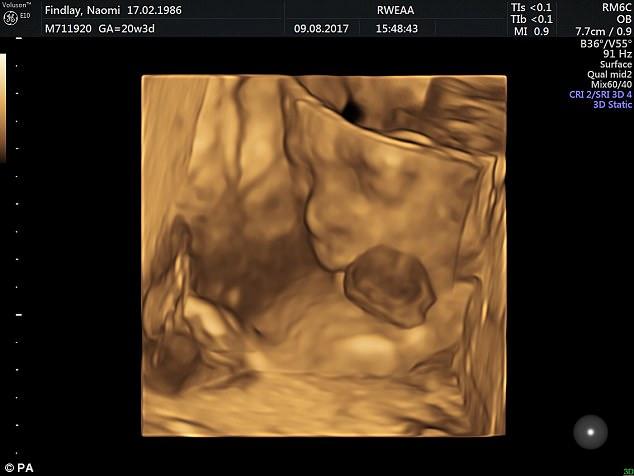

Οι ευτυχισμένοι γονείς της, που απέρριψαν τις αρχικές συμβουλές να τερματίσουν την εγκυμοσύνη, δείχνουν με περηφάνια την κόρη τους, που πίστευαν ότι δεν αποκτήσουν ποτέ. Τώρα, η Βενέλοπι αναρρώνει από 3 πολύ δύσκολες επεμβάσεις για την μετατόπιση της καρδιάς της στο εσωτερικό του σώματός της. Η σπάνια κατάσταση της διαγνώστηκε σε ένα υπερηχογράφημα κατά τον 9ο μήνα της κύησης. «Άρχισα να κλαίω. Η κατάστασή της ερχόταν μαζί με πολλά προβλήματα», δήλωσε η 31χρονη μητέρα της, Ναόμι Φίντλεϊ.

Ο υπέρηχος έδειχνε ότι η καρδιά και μέρος του στομάχου της Βενέλοπι αναπτύσσονταν έξω από το σώμα της.